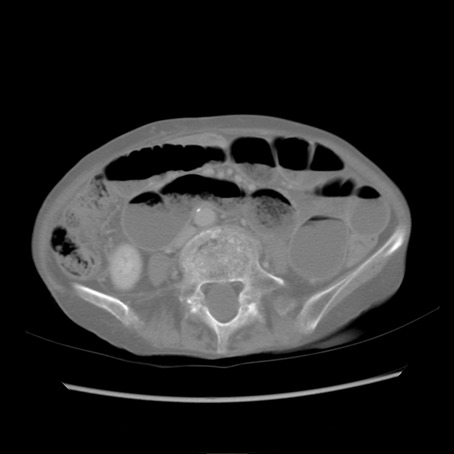

症例25(横断像)

【症例】80歳代女性

【主訴】胸のつかえ感

【現病歴】約9時間前に食後から胸のつかえた感じあり、嘔吐あり、来院。

【既往歴】胃癌(全摘)、胆摘、虫垂炎

【身体所見】心窩部に圧痛あり、反跳痛なし。

【データ】WBC 5700、CRP 0.05